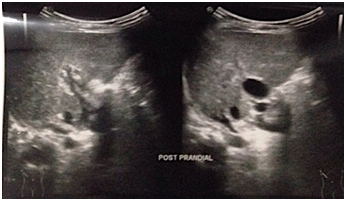

Idiopathic neonatal hepatitis (INH)

INH also known as giant cell hepatitis, accounts for approximately one-third of the cases of NC. It is diagnosed by the presence of the classic pathological findings and the absence of any identifiable cause of cholestasis (Figure 9). There are two different categories: sporadic cases and familial cases that could likely suggest an undiagnosed genetic or metabolic disease. These infants usually have low birth weight. Jaundice is present within the first week of life. Acholic stools are usually absent unless there is severe cholestasis. INH was the common etiology in NC of Bangladeshi infants according to Nahid et al.18 (31.6%) and Karim et al.19 (24.2%) study. On physical examination, liver is enlarged and firm in consistency. Serum bilirubin and transaminases are mildly elevated. Liver biopsy (LB) usually shows lobular disarray with hepatocellular swelling (ballooning), focal hepatic necrosis and giant cell transformation with evidence of extramedullary hematopoiesis. Management is usually supportive with nutritional support, vitamin supplementation and treatment of complications of cholestasis. Prognosis is variable with sporadic cases having very good prognosis with 90% resolution by age 1 year and relatively poor prognosis in familial cases suggesting some inborn errors. 3,10

Figure 9: INH infant

(Picture was taken with permission).